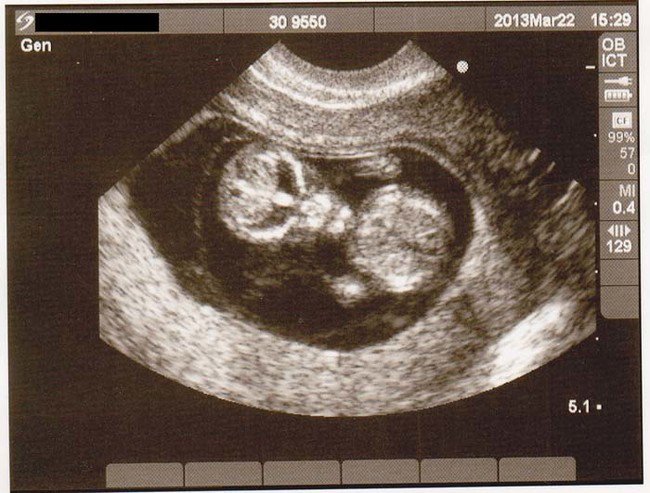

You may make the pregnancy a multiple birth, and give her William and/or another human child to change her level of anguish.